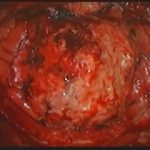

摘出 前

摘出 中